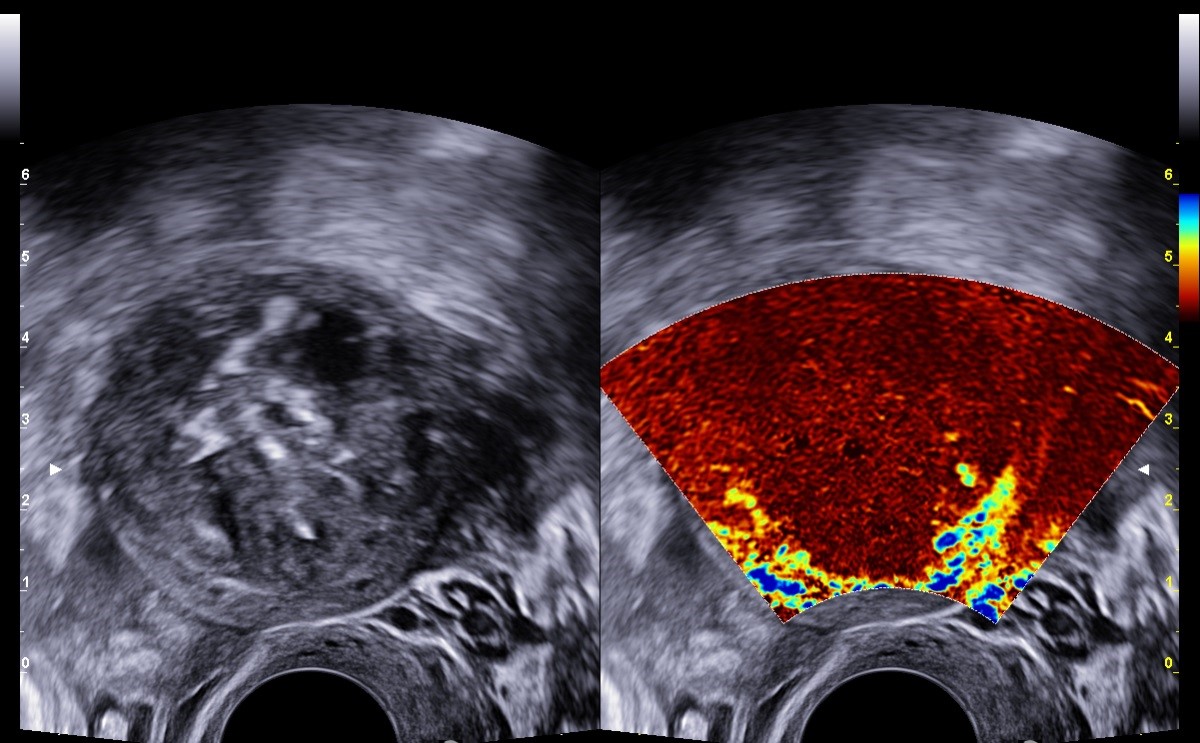

Trattare i fibromi con le microonde, senza bisturi e per via transvaginale. L’intervento, primo in Europa, è stato effettuato dal ginecologo Alessandro Fasciani presso il Polo chirurgico della Casa della Salute di Genova. La paziente, 38enne, è entrata nella struttura alle 8.30 del 20 febbraio e ne è uscita alle 12.30, dopo aver effettuato l’intervento di coagulazione di un fibroma uterino (miolisi).

Da anni il dottor Fasciani utilizza tecniche innovative per il trattamento dei fibromi uterini e ha introdotto in Italia la tecnica dell’ablazione con radiofrequenza con accessi combinati (ecografico transvaginale, laparoscopico e isteroscopico) scelti sulla base della posizione dei miomi nell’utero. Fasciani utilizza la tecnica dal 2017 e ha portato ottimi risultati: “Quasi 9 donne su 10 hanno risolto evitando l’asportazione dell’utero, o dei fibromi per via chirurgica”, spiega Fasciani, contattato da LaPresse, chiarendo che “questa tecnica può evitare il ricovero ospedaliero ordinario soprattutto quando applicata su miomi non superiori ai 5-6 centimetri” . “La miolisi è oggi sempre più richiesta dalle donne perché permette un recupero rapido – prosegue – con ritorno al lavoro fin dal giorno successivo e la possibilità di avere una gravidanza poco dopo l’intervento”.

L’ablazione con radiofrequenza (Arf), prevede l’utilizzo di una temperatura elevata per coagulare il tessuto malato dell’utero risparmiandone le aree sane. “La metodica è affidabile, efficace e un atto chirurgico ‘leggero’ – sottolinea Fasciani – usato da anni nel trattamento dei tumori soprattutto del fegato, dei reni e della tiroide”.

L’ablazione con radiofrequenza (Arf), prevede l’utilizzo di una temperatura elevata per coagulare il tessuto malato dell’utero risparmiandone le aree sane. “La metodica è affidabile, efficace e un atto chirurgico ‘leggero’ – sottolinea Fasciani – usato da anni nel trattamento dei tumori soprattutto del fegato, dei reni e della tiroide”.“La sfida di questi anni è stata semplicemente quella di trasferire questa tecnica nel campo della ginecologia – continua – lavorando su tecnologia e dispositivi dedicati ai tessuti da trattare. Attualmente, grazie a queste innovazioni che garantiscono elevati tassi di precisione e sicurezza, più del 90% dei miomi uterini viene eseguita con sonda ecografica per via vaginale”. La tecnica dà ottimi risultati anche nel trattamento dell’adenomiosi (endometriosi dell’utero) , “ove la chirurgia tradizionale ha alti tassi di fallimento e complicanze”.